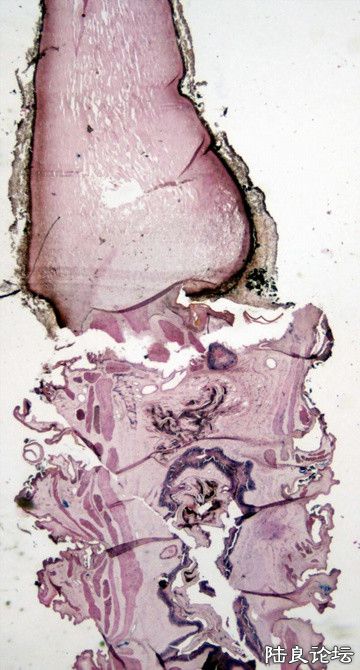

我将冬虫夏草制成切片,到显微镜下观察一下。(见图3、4)

7.jpg

图3:下半部是虫体 上半部是“草”

8.jpg

图4:红色是虫体的肌肉(平滑肌),浅蓝色竹节样细丝是霉菌菌丝